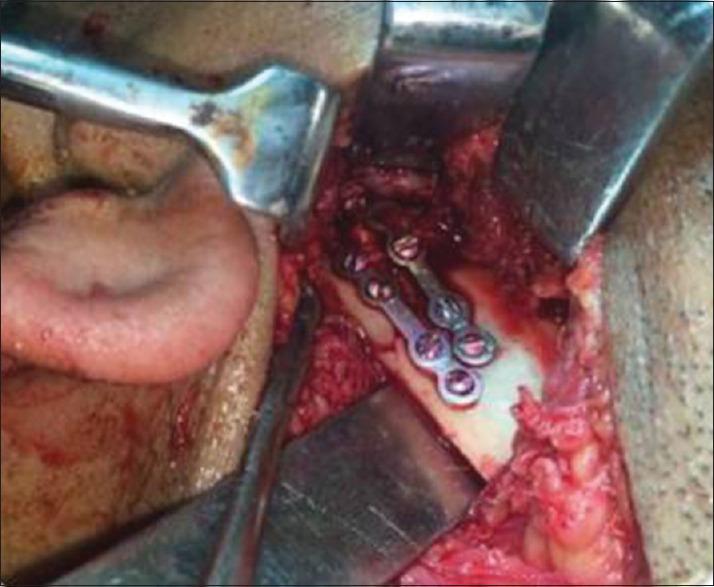

This randomized prospective study was conducted on thirty patients who visited the Department of Oral and Maxillofacial Surgery, Government Dental College, Srinagar, with condylar fractures. All fractures were displaced; either angulated between 10° and 45° and the ascending ramus was shortened by >2 mm to <15 mm. Patients were divided into two groups after satisfying the inclusion and exclusion criteria - Group I (closed treatment) and Group II (open reduction) (15 implants in each group). In Group I, patients were treated by mandibulo-maxillary fixation using arch bar and elastics for 4 weeks, and in Group II, patients were treated by ORIF using two 1.5-mm miniplates. Follow-up was done at 1 month, 3 months, and 6 months. Our postoperative evaluation included five parameters - maximal interincisal opening, protrusion, lateral excursion on fractured and nonfractured sides, anatomical reduction, and pain and malocclusion. Nonparametric data were compared for statistical significance with Chi square test and parametric data with an independent sample's -test ( < 0.05).

本随机前瞻性研究针对30例因髁突骨折就诊于斯利那加政府牙科学院口腔颌面外科的患者开展。所有骨折均有移位;成角10°至45°,升支缩短>2mm至<15mm。满足纳入和排除标准后,患者被分为两组——第一组(闭合治疗)和第二组(切开复位)(每组15例)。第一组患者采用牙弓夹板和弹力牵引进行下颌-上颌固定治疗4周,第二组患者采用两个1.5mm微型钢板进行切开复位内固定术治疗。在1个月、3个月和6个月进行随访。我们的术后评估包括五个参数——最大切牙间开口度、前伸、骨折侧和非骨折侧的侧向运动、解剖复位以及疼痛和咬合紊乱。非参数数据采用卡方检验比较统计学显著性,参数数据采用独立样本t检验(P<0.05)。